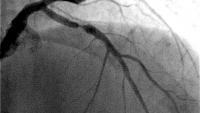

As part of an academic medical center, research is core to the mission of our interventional cardiovascular team. Our physicians are pioneers in investigating innovative treatment solutions for patients with cardiovascular disease. We are dedicated to the research of interventional cardiology to further our knowledge about new techniques and technologies. Many of our clinicians have been, and continue to be, national leading principal investigators for clinical trials and are instrumental in furthering the technologies in virtually every area of interventional cardiac and vascular therapies.

The mission of the Columbia Interventional Cardiovascular Care Clinical Research Group is to provide innovative and compassionate care to our patients through participation in clinical trials, to advance the state of knowledge in the field of interventional cardiology, and to broadly disseminate our findings for the benefit of existing and future patients. We strive to employ highly qualified researchers in a collaborative teaching environment that promotes the importance of responsible medical research.